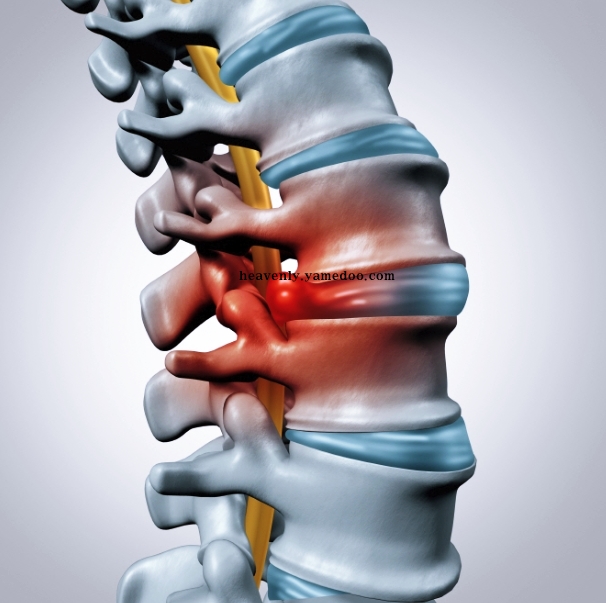

목디스크는 경추 즉 목뼈 사이의 디스크가 빠져나오거나 뼈조직이 목으로 지나가는 척추 신경을 압박하여 통증을 발생시키는 것입니다. 발생 원인으로 알아보면 평소 바르지 못한 자세, 접촉사고, 충격여파 등 다양한 요인들이 있습니다.

가는세월 절대로 막지 못합니다. 세월이 흘러 나이를 먹으면 자연적으로 발생하는 것이 목디스크 증상 이기도 합니다. 그 이유는 인간의 추간판이 탄력성을 잃게되어 섬유륜에 균열이 생긴다고 합니다. 따지고 보면 나이를 먹으면 먹을수록 자연스럽게 발생하는 것이라고 생각하면 되겠습니다.

이는 디스크 수핵이 탈출하여 척수가 눌리게 되면 팔의 힘이 약화 되는데 축수가 압박된 정도에 따라서 한 쪽 팔의 마비 또는 저림 증상이 나타나며 손가락 감각 이상 증세를 보이기 때문입니다.